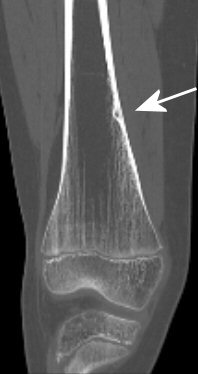

- Osteoidosteom: litet nidus med periost runt, syns bäst på DT. Ger nattlig värk hos barn, smärtlindras bra med COX-hämmare. Läker spontant, kan behandlas med RF-behandling.

Exempel på osteoid osteom i distala femur